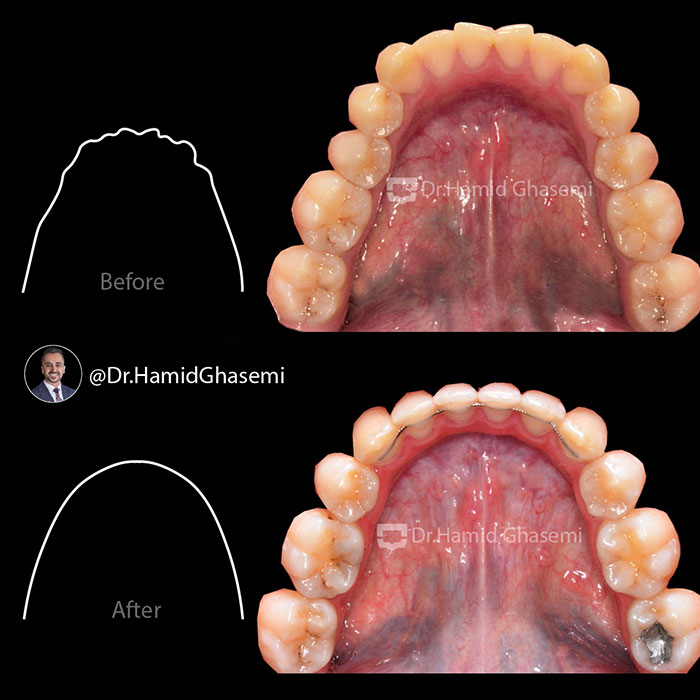

درمان ارتودنسی بدون جراحی در کیس bimaxillary dentoalveolar protrusion (جلوزدگی فک بالا و پایین) با کشیدن دندانهای پرمولر دوم در مدت ۲۰ ماه انجام شد. بهبود بافت نرم صورت و حالت لبها در نمای نیمرخ فتوگرافی و رادیوگرافی لترال کاملا مشهود است.

️Non surgical orthodontic treatment of case with bimaxillary dentoalveolar protrusion done by extraction of 2nd bicuspids within 20 months. Improvement of soft tissue profile and lips posture are obvious in profile photography and lateral ceph xray.